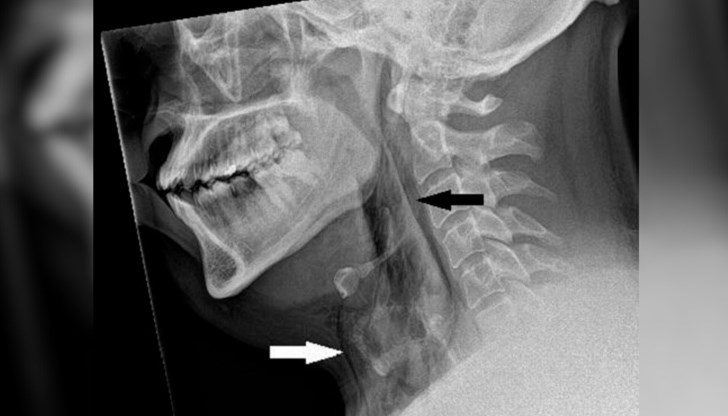

След това медицинският персонал извършил рентгенова снимка, която разкрила хирургичен емфизем; често причинено от нараняване, това е, когато въздухът навлезе и се задържа под кожата. Компютърна томография, извършена веднага след това, открива разкъсване на трахеята на мъжа с дължина 2 милиметра, ширина 2 милиметра и дълбочина 5 милиметра.